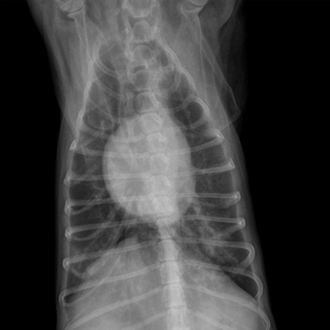

심장 응급 질환

(이첨판 폐쇄부전증 · 폐수종)

심장 기능 저하로 호흡 곤란이나 급성 악화가 발생하는 질환입니다.

빠른 영상·청진 평가 후 즉각적인 안정화 치료가 중요합니다.